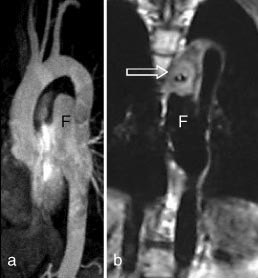

Ved medfødte aortabueanomalier inkludert coarctatio aortae vil MR med MRA kunne gi all nødvendig informasjon og erstatte kateterangiografi. Ikke minst ved mistanke om koarktasjon burde MR være førstevalg. MRA gir en fullgod anatomisk oversikt over hele torakalaorta (fig 6), og måling av blodstrømshastighet i det stenotiske området kan brukes til å beregne trykkgradienten over stenosen.

Ved aortadisseksjon er CT og MR likeverdige når det gjelder å påvise disseksjonen, men MR med kontrastforsterket MRA gir en bedre angiografisk oversikt og kan lettere fremstille det falske lumens kommunikasjon med det ekte lumen. Kontrastforsterket MRA kan med fordel utføres som to opptak med et kort tidsintervall. Det første opptaket vil kunne fremstille tidlig kontrastfylling av det ekte lumen, mens det forsinkede opptaket vil kunne vise forsinket kontrastfylling av det falske lumen.

Aortaaneurismer fremstilles som regel adekvat med både CT og MR. Kontrastforsterket MRA har den svakhet (i likhet med kateterangiografi) i forhold til CT at bare karlumen og ikke trombemassene vises. Konvensjonell MR kan imidlertid vise trombene (fig 7).